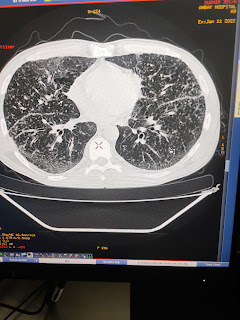

Middle lobe consolidation with bronchiectasis

PA view of chest x ray show dense lesion silhouetting medial border of heart with ovious outline of right dome of diaphragm indicating involvement of middle lobe ( which is ovious in lateral chest x ray .

What are possible causes ?

TB

Non tuberculosis mycobacteria

Ciliary dyskinesis